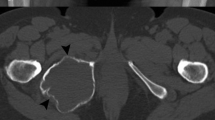

Giant cell tumor of bone (GCTB) is an osteolytic neoplasm that usually develops in the metaphysis to epiphysis of a long bone (such as the femur or tibia) or in the axial skeleton (such as the spine or sacrum) of young to middle-aged adults [1]. GCTB may occur in the metaphysis without involving the epiphysis, particularly in children whose growth plates are still open. Clinically, GCTB behaves as a locally aggressive tumor, sometimes with destruction of bone cortex and extraosseous invasion. GCTBs frequently show local recurrence. Some GCTBs have shown metastasis to the lung, in keeping with the histology of conventional GCTB. In rare instances, GCTB shows malignant transformation to high-grade sarcoma [2].

Histologically, conventional GCTB is composed mainly of three types of cells: mononuclear neoplastic cells, mononuclear histiocytic cells, and osteoclast-like multinucleated giant cells (Fig. 1a) [1]. The mononuclear neoplastic cells have round to spindle-shaped nuclei and various degrees of mitotic figures. Secondary aneurysmal bone cyst-like change is often associated with GCTB. The name "giant cell tumor" has been somewhat confusing regarding the nature of neoplastic cells. Recent studies have obtained evidence that mononuclear cells with an osteoblastic precursor phenotype are the true neoplastic element of GCTB, whereas mononuclear histiocytic cells and osteoclast-like multinucleated giant cells are considered non-neoplastic elements [3, 4]. However, mononuclear neoplastic cells and mononuclear histiocytic cells are indistinguishable only by cellular morphology on hematoxylin–eosin stained specimens. Mononuclear neoplastic cells can be identified by osteoblast-related markers such as RUNX2 and p63 [3]. In contrast, mononuclear histiocytic cells and osteoclast-like multinucleated giant cells are positive for CD68.